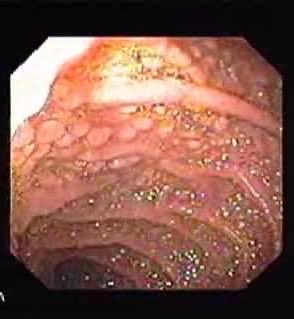

2️⃣ Small Intestinal Ulcers

📍 Seen in: SLE or vasculitis (PAN, APLA)

🔎 Jejunal or ileal ulcers ± perforation

🔬 Ischemic or inflammatory on histology

📌 Consider CT angiogram + biopsy Image